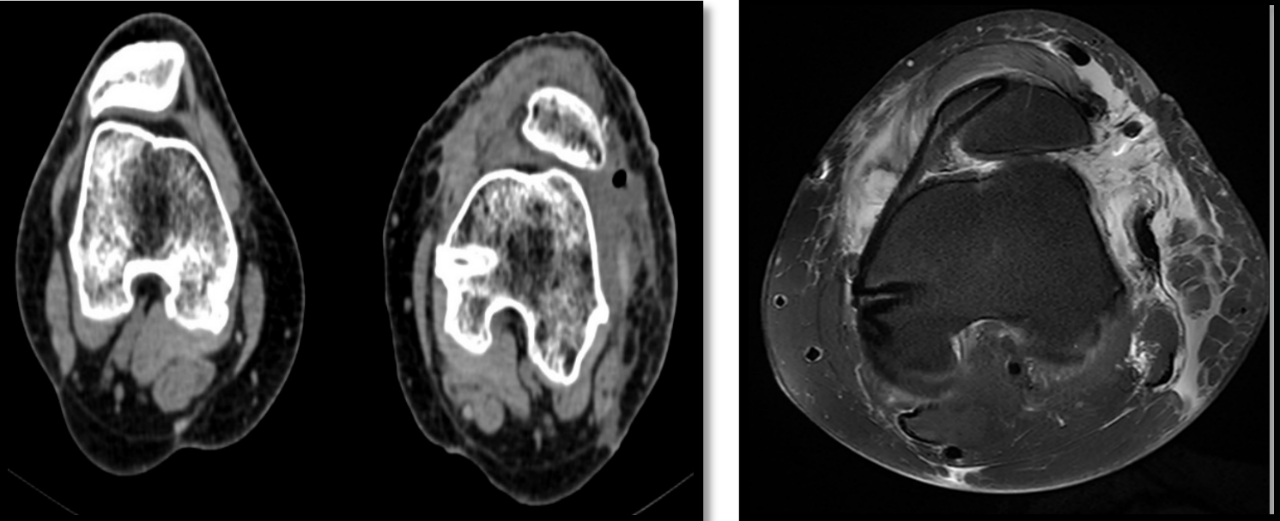

【影像学检查】

【诊断】左侧髌骨固定性脱位